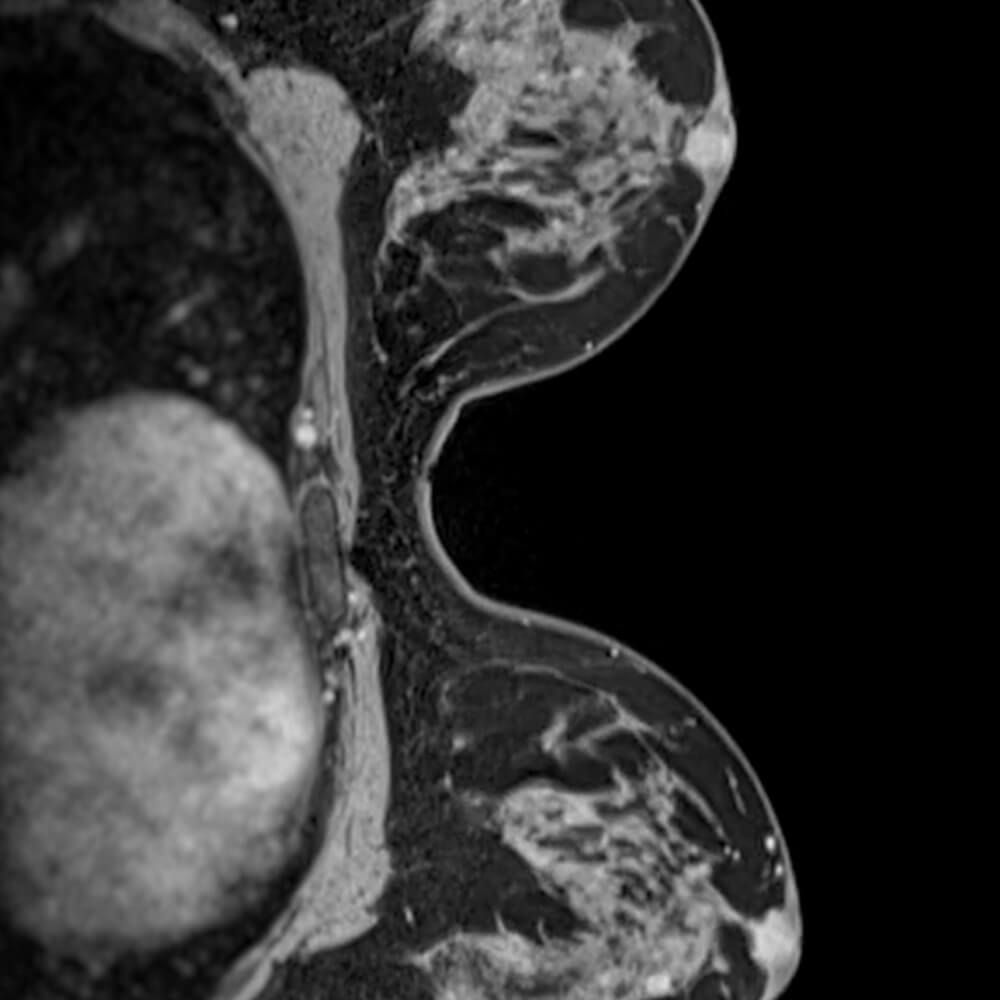

Our Breast MRI screening scan provides detailed images of both breasts using contrast-enhanced MRI. It is especially helpful for women with dense breast tissue on mammogram, offering an additional layer of information to support regular breast screening and conversations with your doctor. This is a private, self-pay service and is not covered by OHIP.

- Intravenous contrast (gadolinium) to highlight areas of concern

Contrast Enhanced Detail

Intravenous contrast/gadolinium highlights areas of abnormal blood flow

This Breast MRI screening scan is designed as an adjunct to regular breast care, especially for women with dense breast tissue, and is not meant to replace mammograms, ultrasound, or your doctor’s advice.